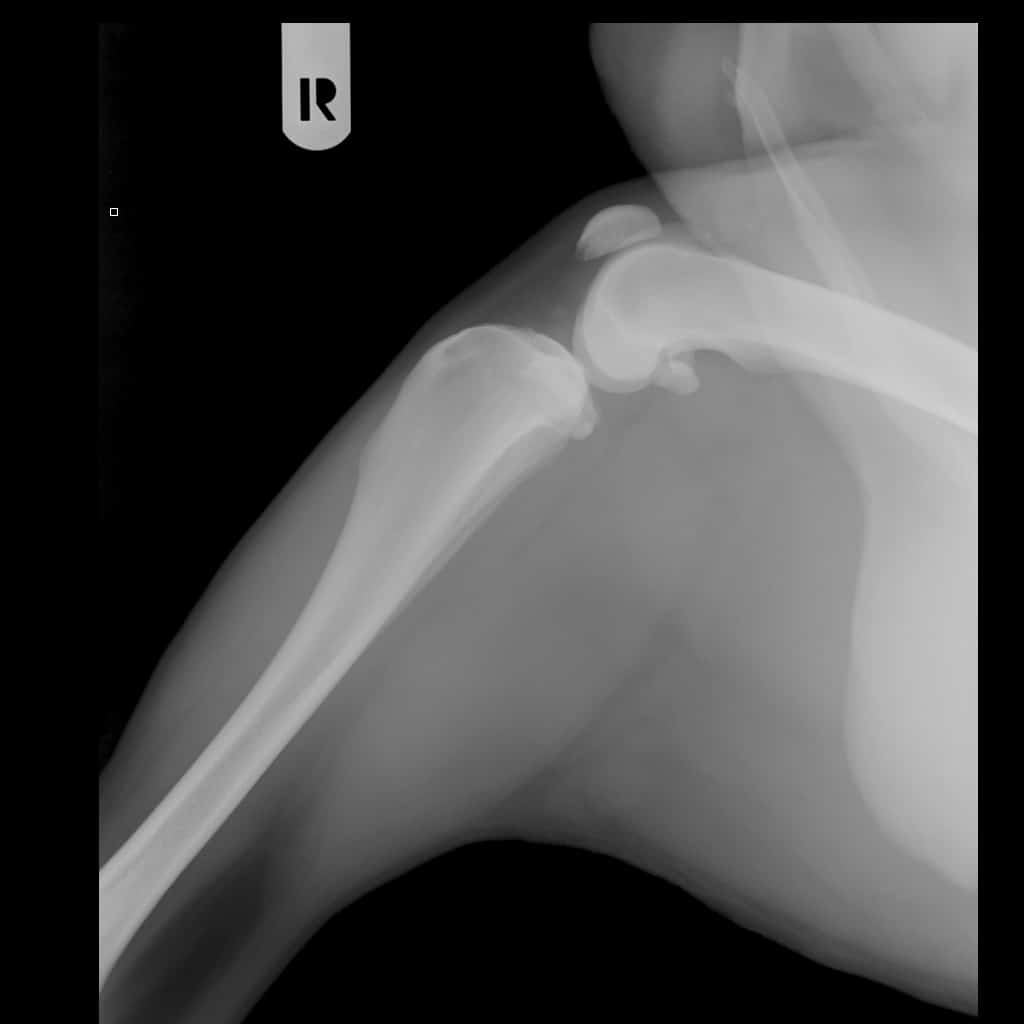

Eerst moesten we op intake en werden er nog wat extra foto’s gemaakt om meer duidelijkheid te creëren. Een paar weken later vond de operatie plaats.

Toen de operatie was afgelopen, werd er opnieuw een foto gemaakt, met de titanium korf in mijn been. Dat was best indrukwekkend. Bij het wakker worden keek ik in de bezorgde gezichten van mijn bazen. Ik had nog zoveel pijn en piepte alles bij elkaar. Ook toen we eenmaal thuis waren, bleef ik maar piepen… Ik vond het heel moeilijk om mijn behoefte te doen. Ik wilde buiten niet plassen met de druk van een handdoek onder mijn buik. Ook in de tuin wilde ik niet plassen, want dat doe ik nooit, en in huis wilde ik het al helemaal niet laten lopen. Mijn bazin zei steeds: “Beer, laat het maar komen, ik ruim het wel op. Je kan er toch niks aan doen, vriend.”